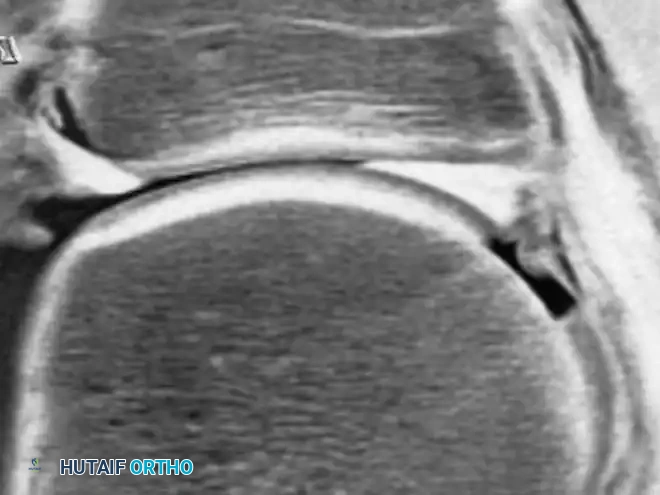

تم توجيه الكثير من الجهود الطبية لتقييم الشفا الحقي. في الماضي، كانت مراجعات دقة الرنين المغناطيسي التقليدي في تقييم الحالات المرضية للشفا مخيبة للآمال بسبب استخدام مجالات رؤية واسعة تفتقر إلى الدقة الكافية. ومع ظهور تقنية تصوير المفاصل بالرنين المغناطيسي مع حقن الصبغة، تحسنت بشكل كبير رؤية الشفا الغضروفي.

يُظهر الشفا الحقي تباينا طبيعيا واسعا لدى الأفراد الذين لا يعانون من أعراض. أما في المرضى الذين يعانون من أعراض ميكانيكية في الورك أو احتمال وجود انحشار أمامي، فإن إضافة حقنة مخدرة أثناء التصوير تعتبر مفيدة جدا لتقييم ما إذا كان مصدر الألم من داخل المفصل.

لا تقتصر قوة الرنين المغناطيسي على مفصل الورك فحسب، بل تمتد لتشمل المفاصل الأخرى كالركبة، مما يثبت فعالية هذه التقنية في كشف أدق التفاصيل التشريحية والمرضية في العظام والغضاريف. نستعرض هنا بعض الأمثلة التي توضح دقة الرنين المغناطيسي في تشخيص إصابات المفاصل:

هذه الصور تؤكد بما لا يدع مجالا للشك أن الاعتماد على الرنين المغناطيسي يوفر خريطة طريق واضحة للطبيب المعالج، سواء كان يتعامل مع كيس زلالي، أو كدمة عظمية، أو كسر خفي في صفيحة النمو، أو آفة غضروفية، مما ينعكس إيجابا على دقة التشخيص في مفصل الورك والمفاصل الأخرى.